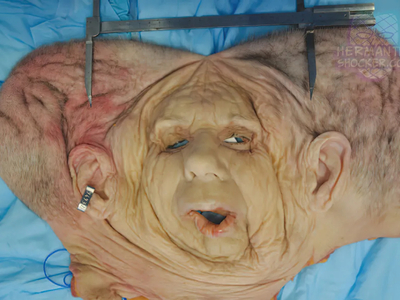

Composite facial allografts have become increasingly popular in the reconstruction of complex facial defects. Good to excellent aesthetic results can be achieved, particularly when a foundation of donor skeleton has been transferred...